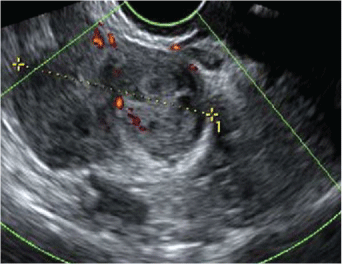

A routine pelvic ultrasound was performed showing bulky uterus with thin endometrium and heterogeneous intracavitary leiomyoma. Pelvic ultrasound showed also a right lateral uterine mass of 45 mm arising from the corpus uteri and partially vascularized (Figure 1). In addition, the patient did not have any other radiological examinations such as CT scan or MRI.

Figure 1: Ultrasonographic finding of intravascular leiomyoma: Right lateral uterine mass of 45 mm arising from the corpus uteri and partially vascularized. View Figure 1